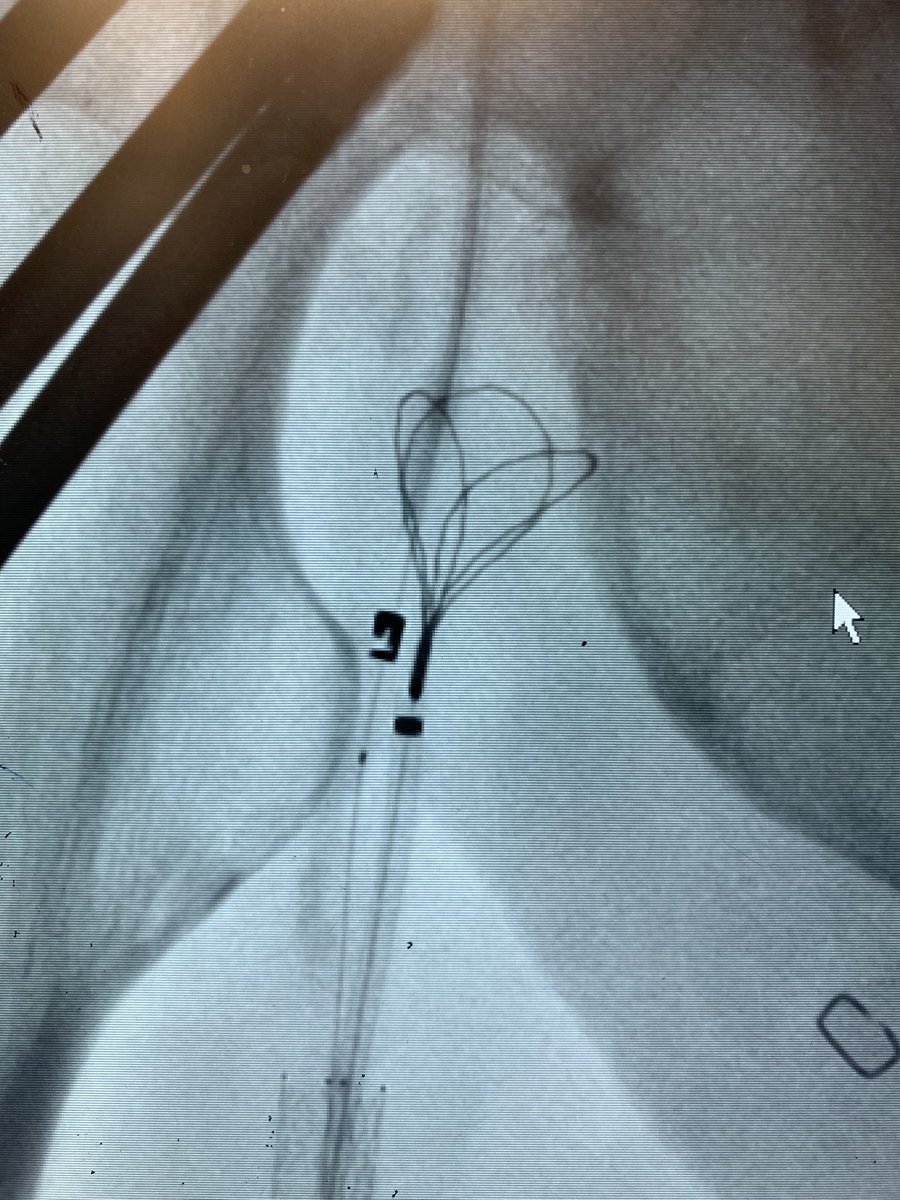

First glimpse of #PTAB w #Detour @endologix 3 week surveillance arterial duplex @ShawnPenn33 @DeanFerreraDO @MarcoShaker @kymbee @tlevin